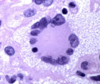

plasma cell features

- Nucleus pushed off to one side (eccentric)

- Chromatin in the nucleus clumps into spheres (clock-face)

- Next to the nucleus there is slightly paler staining- peri- nuclear cytoplasmic clearing –> Golgi due to antibody synthesis